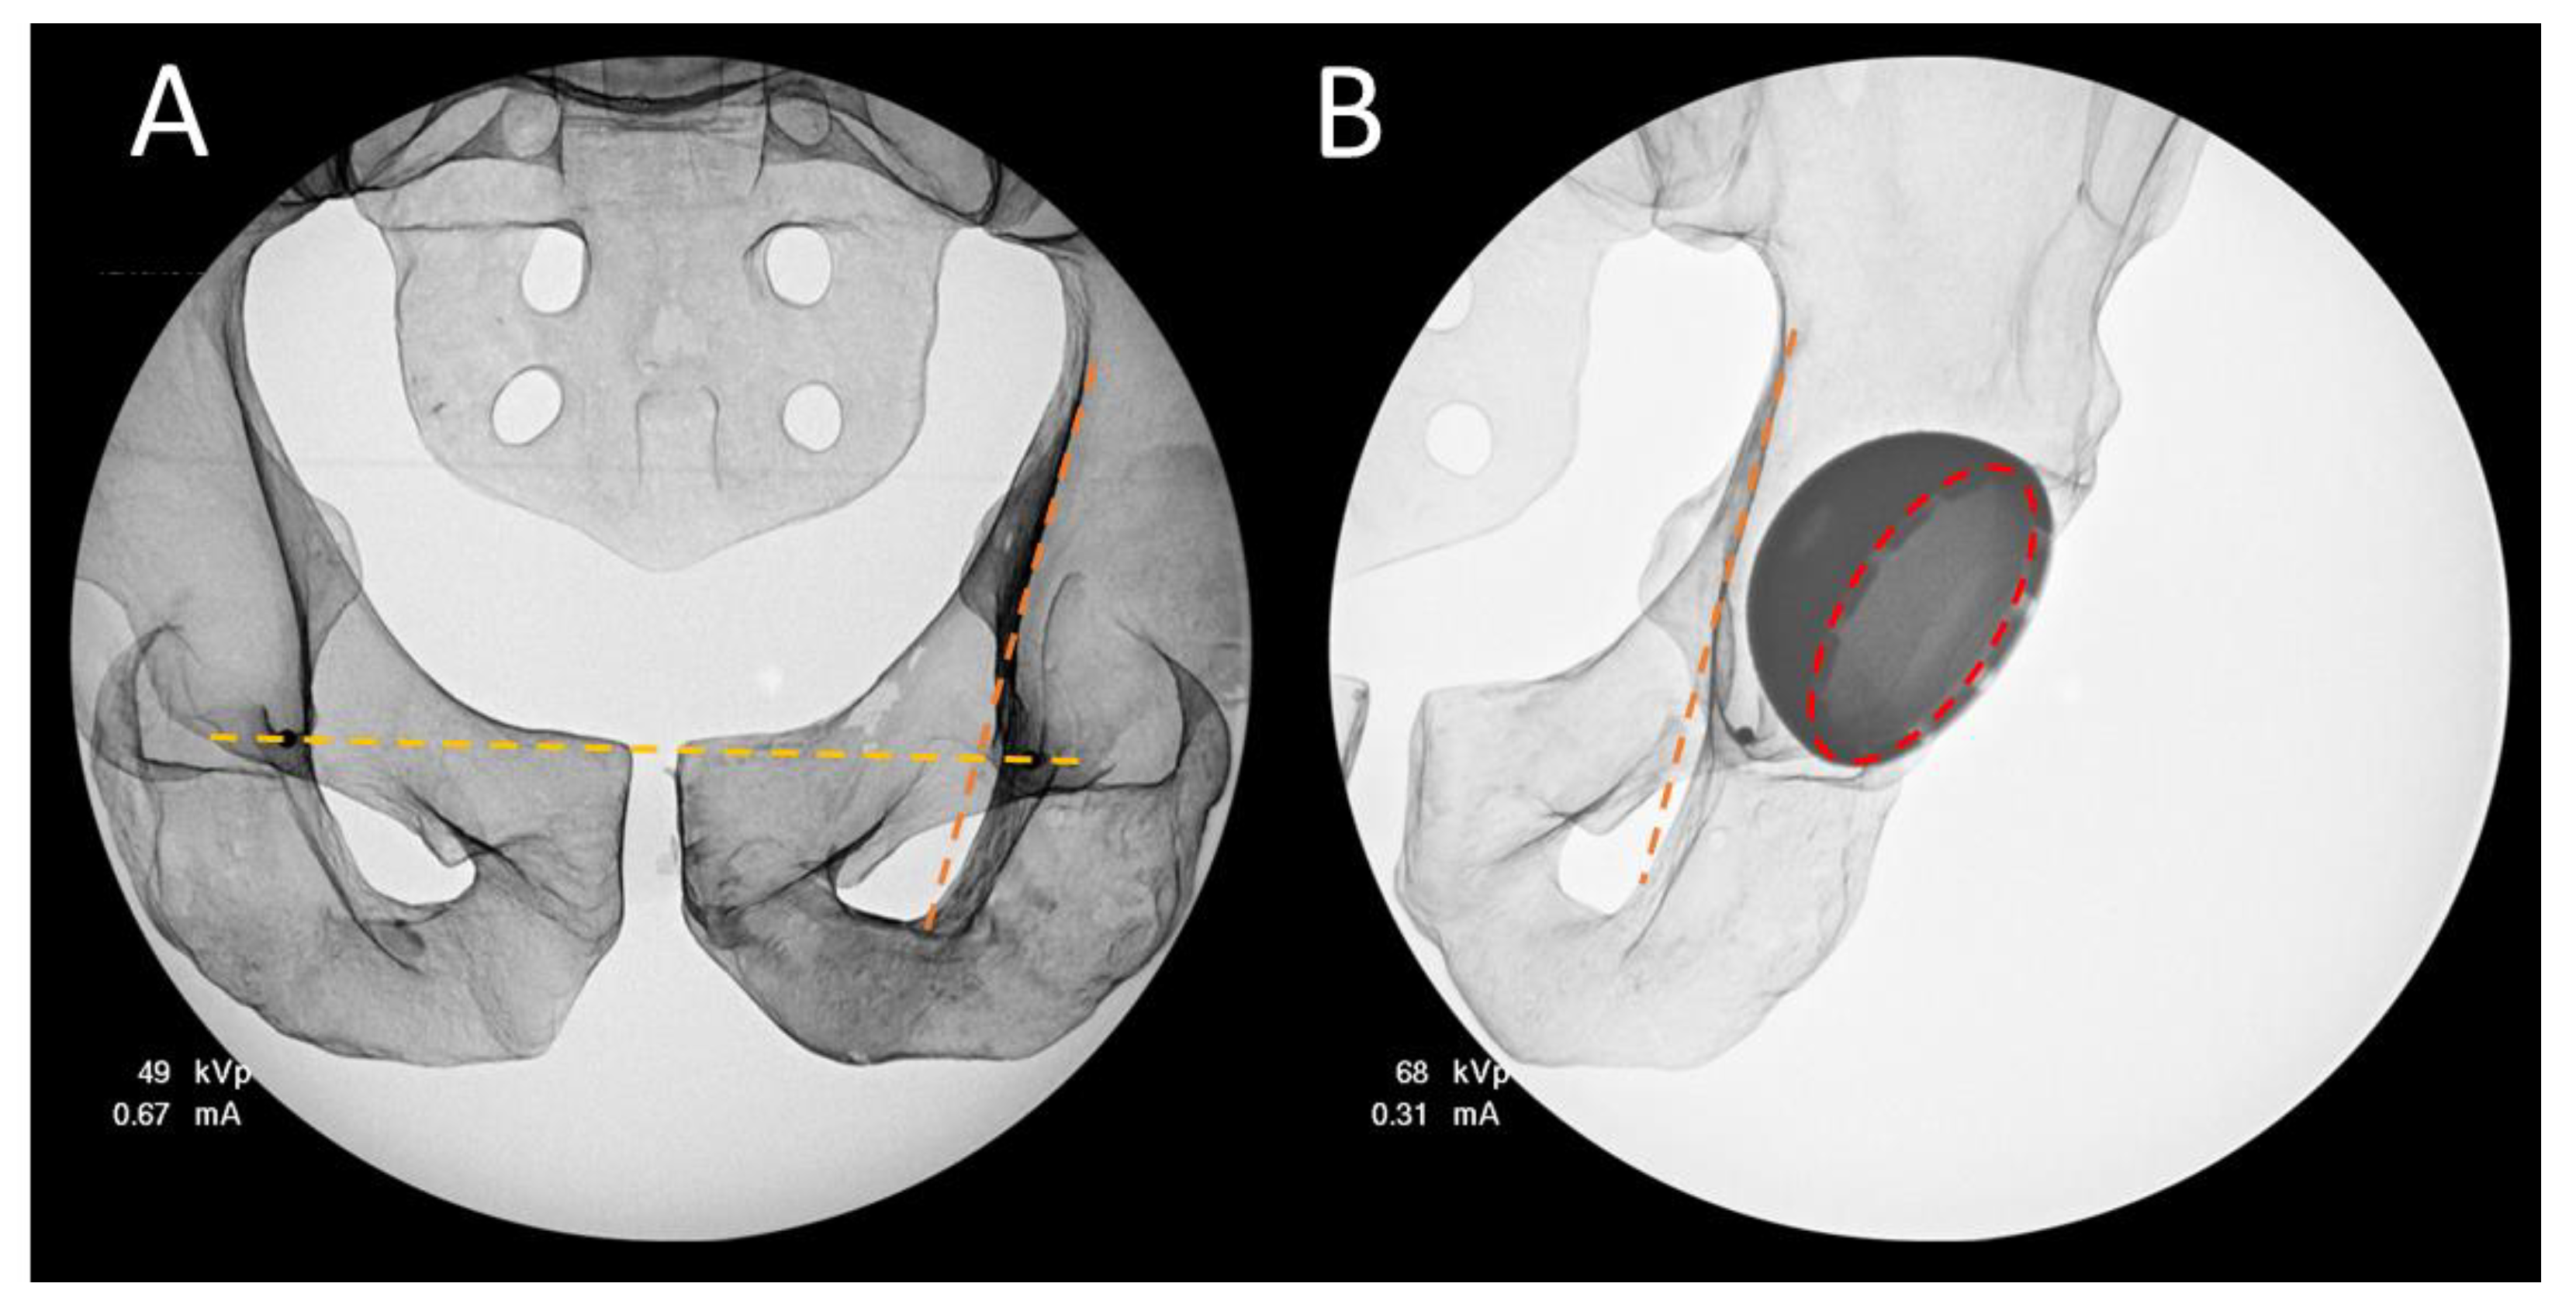

2.4. 2D Analysis